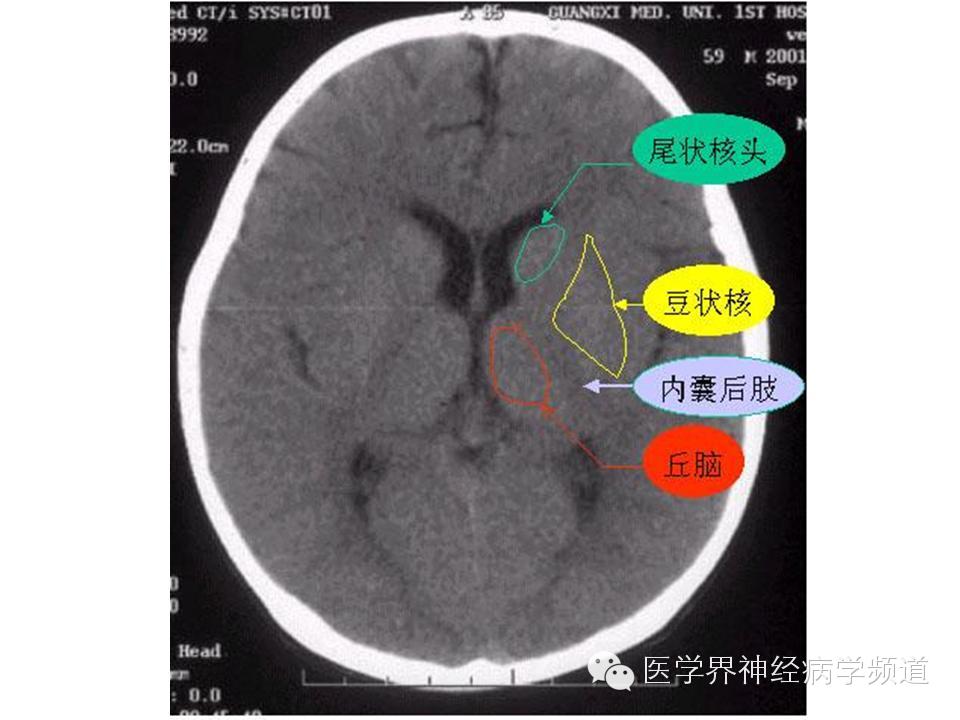

神经影像CT读片step by step